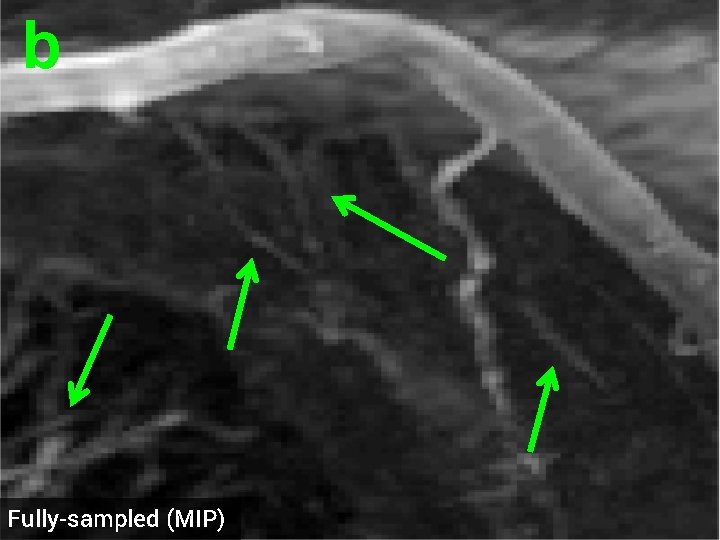

3 -D Compressed Sensing MRA § 512 x 76 voxel MRA dataset obtained from physiobank (see ref. [6]) § Simulated single coil acquisition § Retroactively undersampled at 1. 5 -fold acceleration § Random Gaussian sampling of k-space § 5 d. B additive Gaussian noise § Optimized regularization parameter MIP of original MRA dataset

b Fully-sampled (MIP)

b TV recon, 1. 5 x accel. (MIP) SNR = 14. 53 d. B

b HDTV 2 recon, 1. 5 x accel. (MIP) SNR = 15. 11 d. B

3 -D Quantitative Results Table 3: 3 -D Comparisons. SNR (in d. B) of recovered images with optimal reg. param. Denoising Cell 1 Cell 2 Deblurring Cell 1 CS-MRI Cell 2 Cell 3 Angio, acc=5 Angio, acc=1. 5 Cardiac TV 17. 12 16. 25 19. 02 16. 43 14. 50 13. 87 14. 53 18. 37 HDTV 2 17. 25 16. 70 19. 15 16. 60 14. 87 14. 23 15. 11 18. 56 HDTV 3 17. 68 17. 14 19. 73 17. 43 15. 23 14. 01 14. 70 18. 50 § HDTV outperforms TV in all experiments § HDTV 3 better for denoising and deblurring § HDTV 2 better for CS-MRI